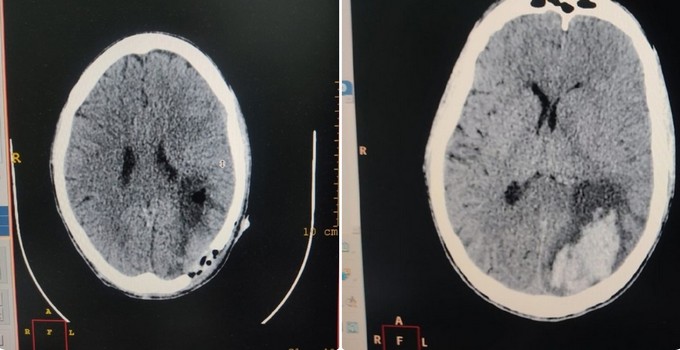

Мужчина в возрасте 33 лет пожаловался на то, что у него в течении трех дней ухудшается зрение. Его сразу же отправили в Серпуховскую областную больницу, где на КТ головного мозга диагностировали геморрагический инсульт с формированием острой внутримозговой гематомы левой гемисферы, гомонимную гемианопсию справа.

Пациент был переведен в нейрохирургическое отделение хирургического стационара. Его в срочном порядке прооперировали. В ходе операции провели трепанацию черепа и удалили внутримозговую гематому. На следующий день пациента уже перевели в палату. Зрение улучшилось, он смог самостоятельно набирать номер на телефоне (ранее это было невозможно).